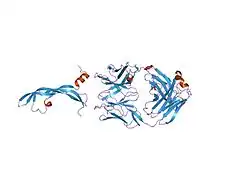

When cells are deprived of oxygen, they increase their production of VEGF-A. VEGF-A mediates the growth of new blood vessels from pre-existing vessels (angiogenesis) by binding to the cell surface receptors VEGFR1 and VEGFR2, two tyrosine kinases located in endothelial cells of the cardiovascular system. These two receptors act through different pathways to contribute to endothelial cell proliferation and migration, and formation of tubular structures.[17]

VEGFR2

The binding of VEGF-A to VEGFR2 causes two VEGFR2 molecules to combine to form a dimer. Following this dimerization, through the action of the receptor itself, a phosphate group is added to certain tyrosines within the molecule in a process called auto-phosphorylation.[18] The autophosphorylation of these amino acids allows for signalling molecules within to the cell to bind to the receptor and become activated. These signalling molecules include VEGF-receptor activated protein (VRAP), PLC- γ and Nck.[19][20][21]

The tyrosine kinase activity of VEGFR1 is less efficient than that of VEGFR2 and its activation alone is insufficient to bring about the proliferative effects of VEGF-A.[27] The major role of VEGFR1 is to recruit the cells responsible in blood cell development.[28]